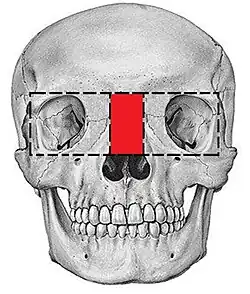

| Hypertelorism as seen in craniofrontonasal dysplasia | |

Hypertelorism is an abnormally increased distance between two organs or bodily parts, usually referring to an increased distance between the orbits (eyes), or orbital hypertelorism. In this condition, the distance between the inner eye corners, as well as the distance between the pupils, is greater than normal. Hypertelorism should not be confused with telecanthus, in which the distance between the inner eye corners is increased, but the distances between the outer eye corners and the pupils remain unchanged.[3]